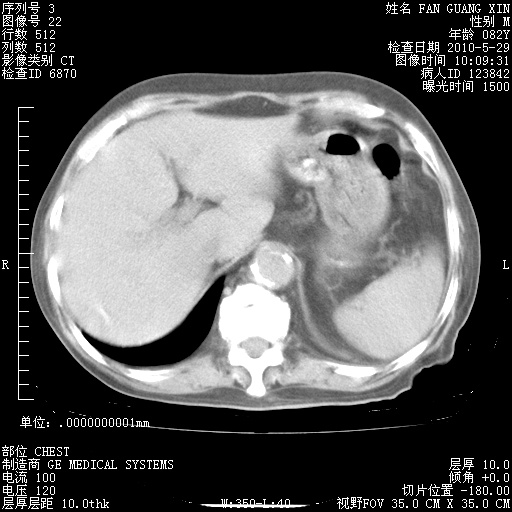

再治疗10天后的肺部CT 纵膈窗

阅读此次胸部CT,肺间质渗出性改变较入院时有吸收。目前从体温、白细胞、中性分叶明显增高,肯定存在细菌感染(发生医院感染哦,若无消化道及泌尿系统等感染的依据,肺部感染可能大)。若你院头孢哌酮舒巴坦钠耐药率较高,同意你的方案,若48小时体温仍高,可考虑使用碳青霉稀类抗菌药物,同时可予超声雾化、注意滴数时加大液体量。白蛋白33.30g/L较低哦,需加强营养等支持治疗。

从白细胞总数和中性比例看好像合并感染。肺部纹理好像比上次多,支气管炎?其他感染?